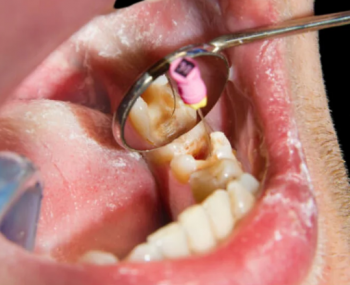

The image shows:

Side-to-side movement being tested.

Visible mobility between the premolar/molar region.

Gingival margin appears slightly inflamed → possible periodontal involvement.